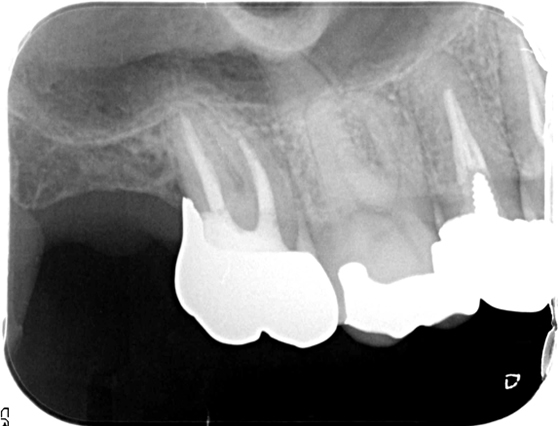

自家歯牙移植

自家歯牙移植は、抜歯が必要な歯(親知らずなど)を、歯を失った場所に移植する治療法です。自分の歯で、見た目や機能を回復することができます。